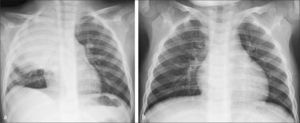

El control radiográfico no debiera ser la regla debiendo reservarse para los casos en que los síntomas son persistentes o recurrentes y pacientes con condiciones clínicas especiales que planteen la posibilidad de una evolución menos favorable, como inmunodeficiencias o fibrosis quística (9). La neumonía redonda constituye una condición en la que se acepta el control rutinario dado que plantea diagnóstico diferencial con patologías congénitas y adquiridas. La resolución de las imágenes de condensación en neumonías bacterianas es más rápida en el niño que en el adulto, habitualmente 7 a 10 días en cuadros no complicados (4) (Figura 2).